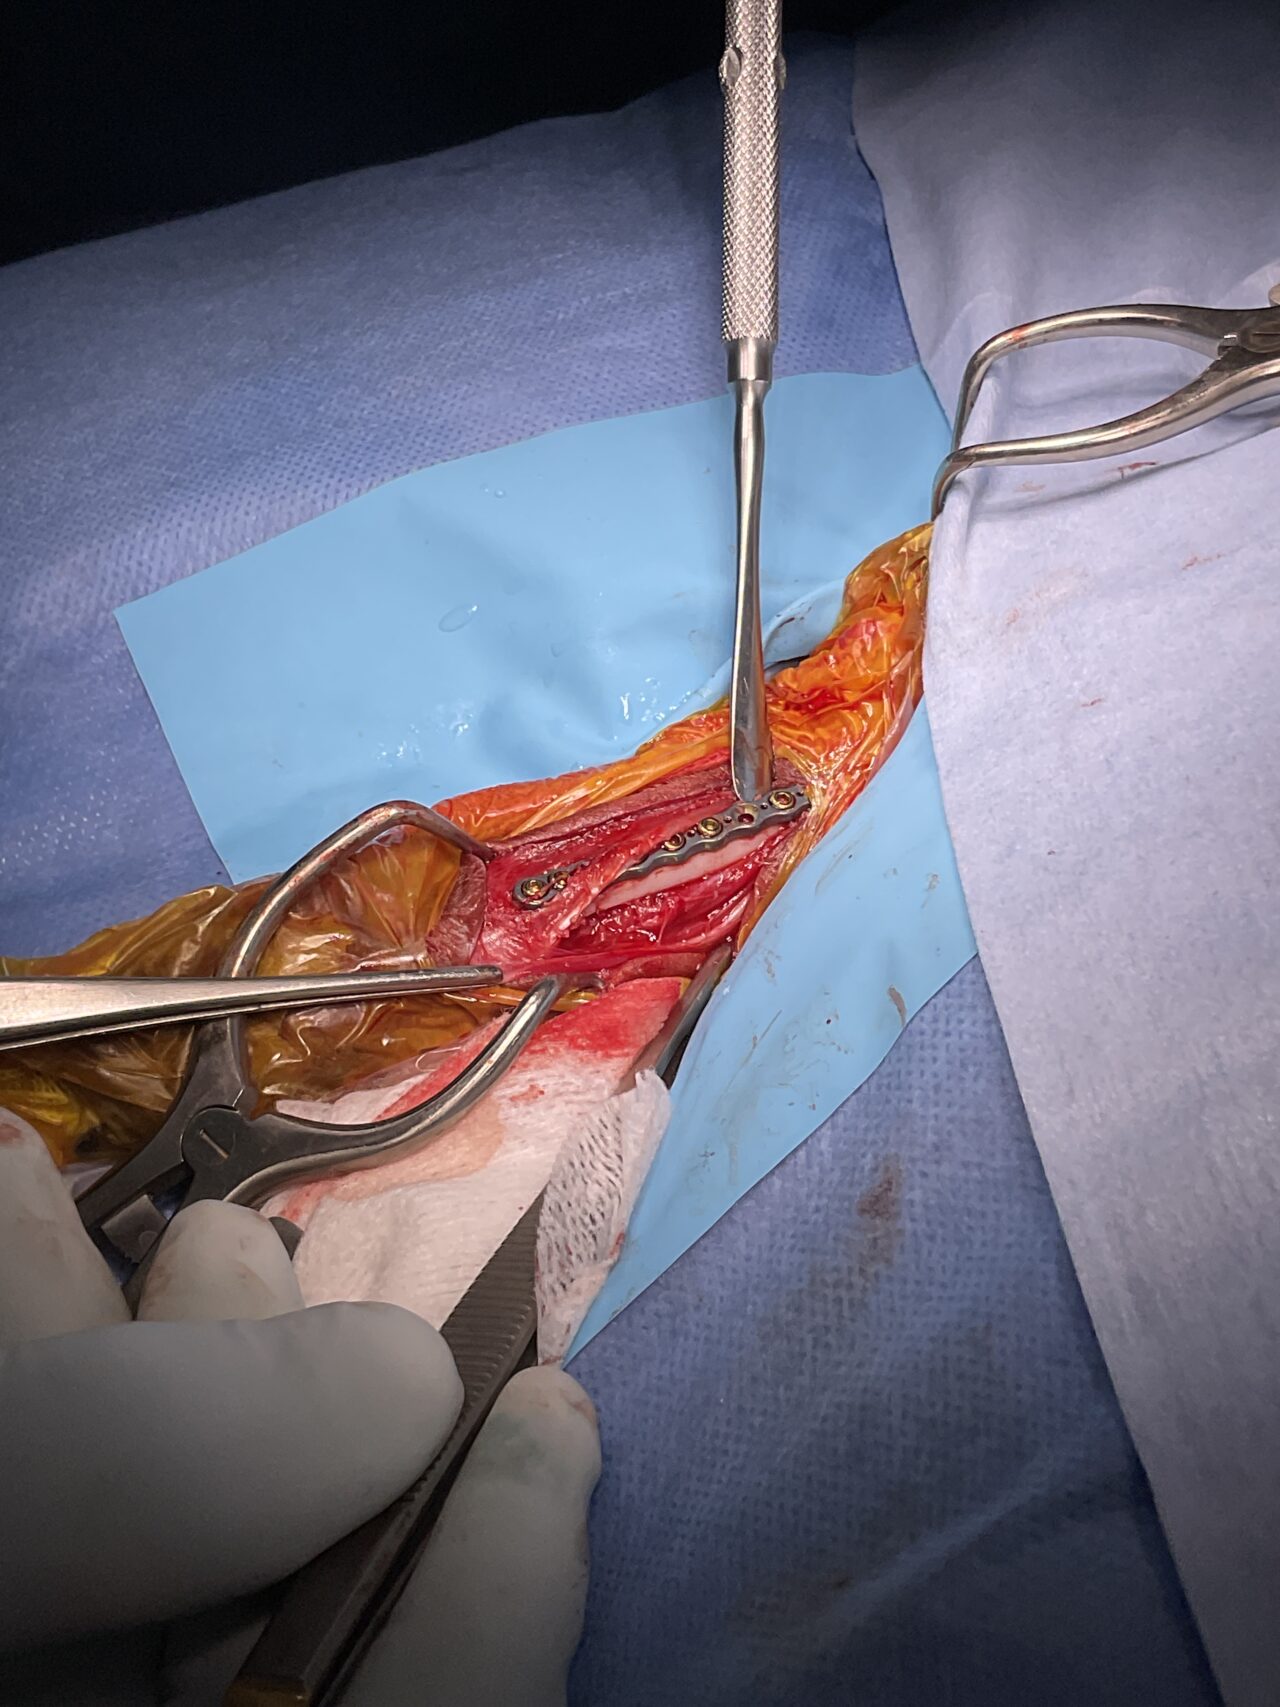

Tea Cup Poodleさんが、ご家族が家に帰宅すると足を挙上しており、着地できないとの事。室内で転倒したか、ソファーなどからジャンプして着地に失敗した可能性があります。エックス線検査で橈骨遠位端骨折が確定されました。1.5mm 3hole タイト ピッチ ストレートプレートで遠位端を固定しました。しばらくは安静が必要です。